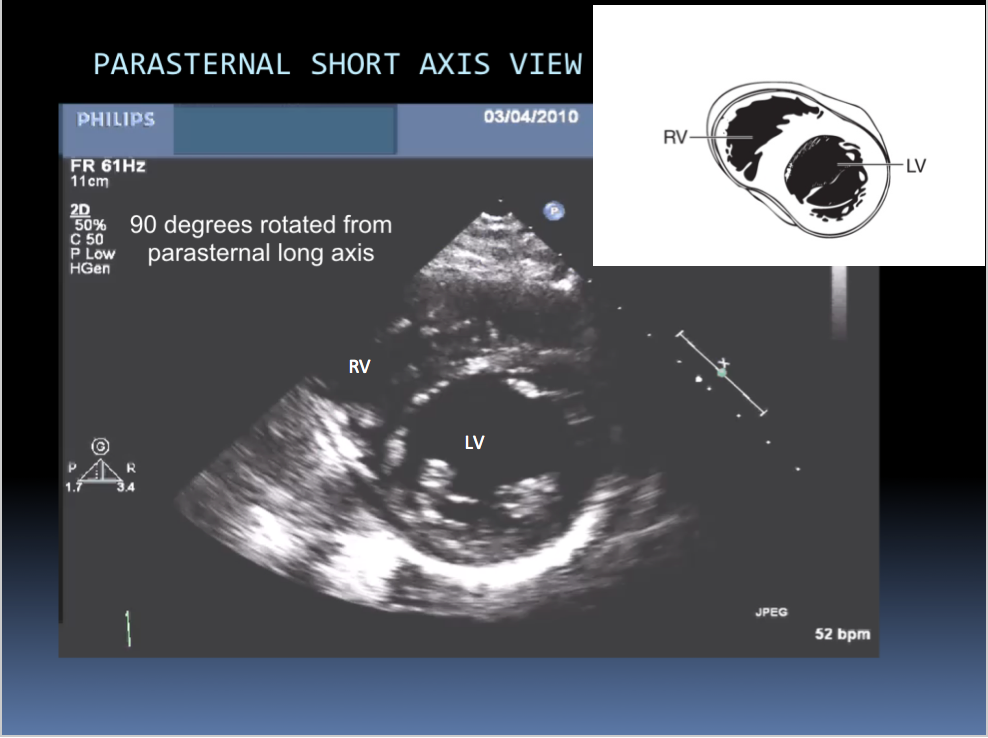

Have 2 primary probe positions, with multiple angulations (multiple ultrasonic beams are transmitted from transducer through a wide arc). The returning signals are integrated to produce 2D images of the heart on a video monitor.

Identify the chambers shown in this image: